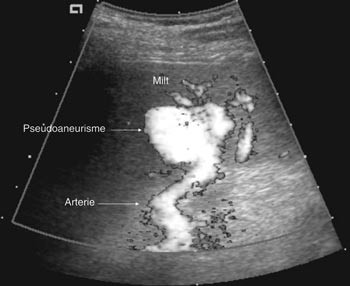

Pasient 2. En 20 år gammel mann ble utsatt for en trafikkulykke. Han var komatøs og ble intubert på skadestedet. CT-undersøkelse ved Ullevål universitetssykehus viste venstresidig pneumothorax og costafrakturer. I milten forelå en laserasjon kaudalt (skadegrad III), men normale funn i hilusnivå (e-fig 4). Pasienten ble observert og overflyttet til lokalsykehus etter tre dager. Seks dager etter traumet ble det gjort en CT-kontroll med arteriell kontrastfase. Denne viste en tilkommet, høytattenuerende lesjon ved milthilus, forenlig med et pseudoaneurisme (e-fig 5). Pasienten ble flyttet tilbake til Ullevål universitetssykehus hvor det ble utført angiografi med embolisering (e-fig 6). Ultralydkontroll samme dag viste opphørt sirkulasjon i lesjonen. Tre dager senere ble pasienten utskrevet.